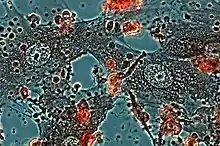

Structurally, epithelioid cells (when examined by light microscopy after stained with hematoxylin and eosin), are elongated, with finely granular, pale eosinophilic (pink) cytoplasm, and central, ovoid nuclei (oval or elongate), which are less dense than that of a lymphocyte.[4] They have indistinct shape and often appear to merge into one another, forming aggregates known as giant cells. When examined by transmission electron microscopy in epithelioid cells in the field of Golgi lamellar complex are taped not only zonated, but also sleek vesicles with dense center, and also great many (more than 100) large granulas with diameters up to 340 nm and with finegranular matrix more light than in macrophage granulas, sometimes with perigranular halo. “The most prominent feature of these cells is the enormous Golgi area; up to 6 individual stacks of Golgi cisternae may be present as well as a few bristle-coated and numerous smooth vesicles”.[5][4] Epithelioid cells have tightly interdigitated cell membranes in zipper-like arrays that link adjacent cells.[3] This cells are central in the formation of granulomas, which are associated with many serious diseases.[4] In granulomas, epithelioid cells perform the functions of delimiting.[3]